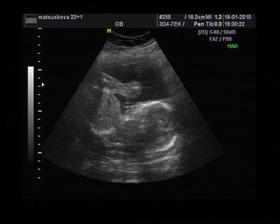

8/10 jsme se byli podívat u paní doktorky, zda testy nelhaly - a ono n e. Puclík měřil 0,37cm a co je důležité - srdíčko už funguje. Táta s Pepínem byli v ordinaci s námi, a když se na monitoru objevilo mimi, tak ho Pepíno pozdravil - udělal mu "ahoj" 🙂 oba nás to s Honzou dojalo. Další kontrola 22/10.